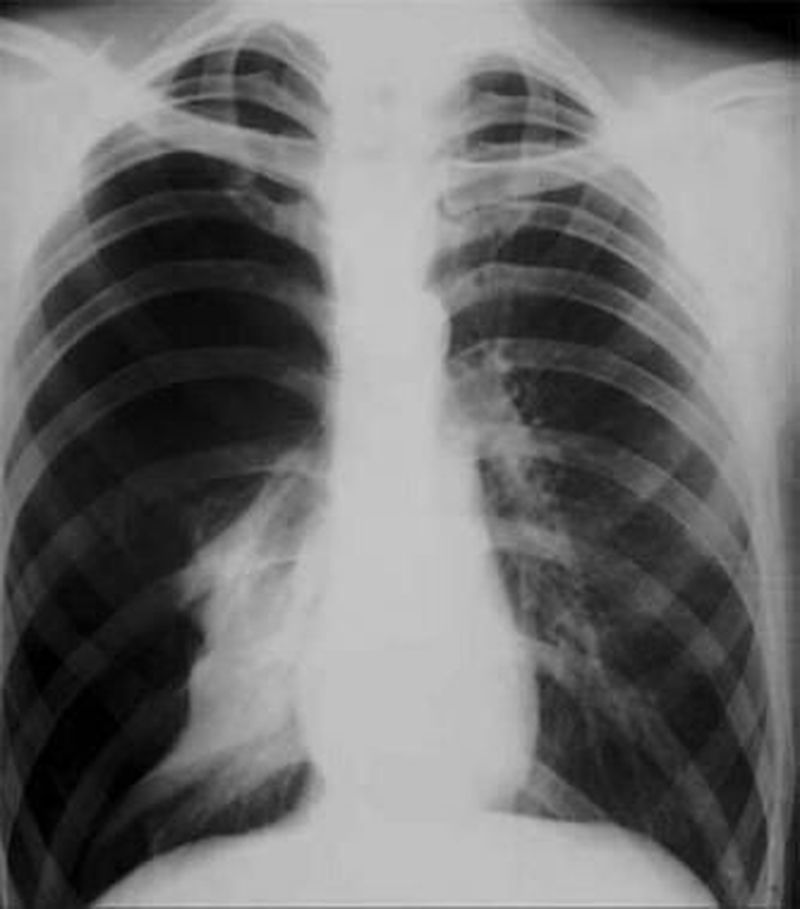

Radiograph of a patient with a complete right-sided pneumothorax due to a stab wound.